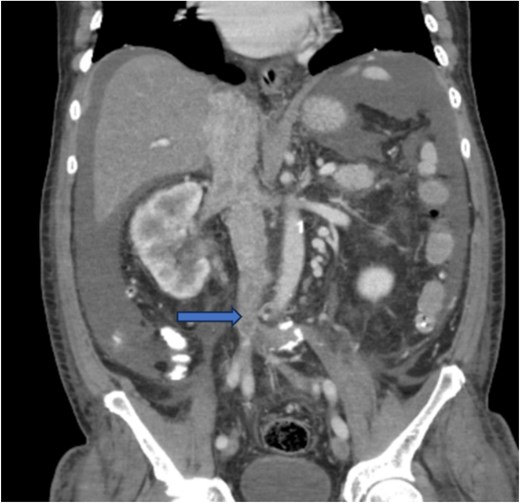

Diagnostic imaging began with a chest X-ray that indicated bilateral pleural effusions. An abdominal ultrasound detected a 4.6 × 4.2 × 4.3 cm echogenic lesion in the right hepatic lobe. Further imaging with a computed tomography (CT) scan of the chest, abdomen, and pelvis revealed a large mass originating from the posterior aspect of the right mid-kidney consistent with RCC (Fig. 1). The mass associated with thrombus extended into the renal sinus and collecting system, traveled along the right renal vein to the inferior vena cava (IVC), and projected into the right atrium (Figs 2 and 3). During hospitalization, bilateral lower extremity pain led to the diagnosis of bilateral deep vein thromboses via duplex venous ultrasound. Echocardiography showed normal left ventricular ejection fraction, impaired diastolic filling, mildly increased ventricular wall thickness, and an echogenic mass extending from the right atrium into the IVC consistent with the tumor thrombus.

CT chest abdomen and pelvis with contrast showing tumor thrombus is seen within the IVC extending over a long distance from the level of the renal vein cephalad into the right atrium.